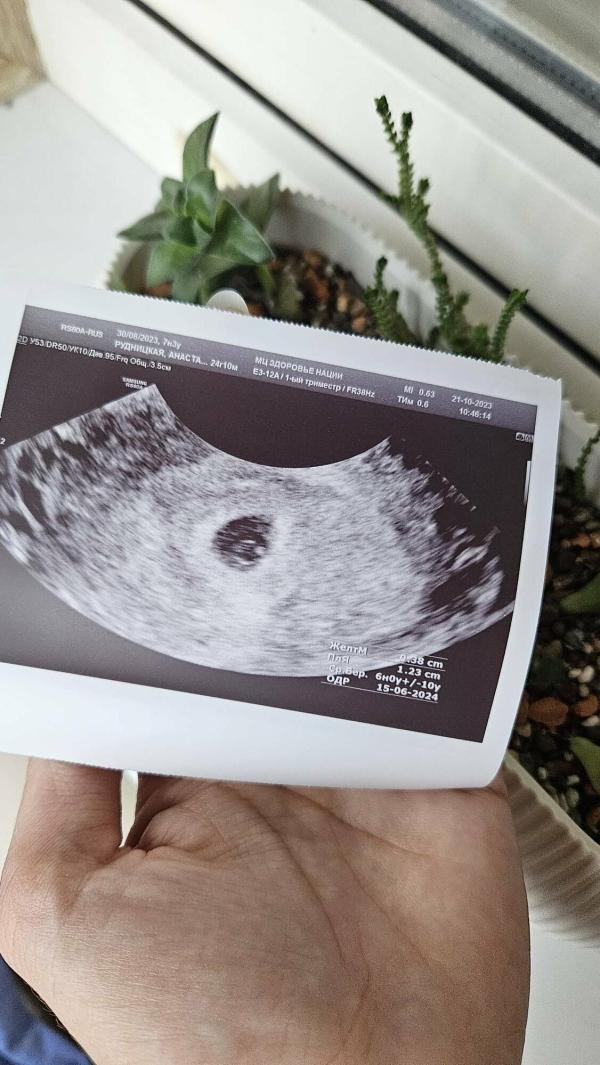

Где наша рисинка?

post image

Вот мы тебя и нашли наша маленькая рисинка❤️🤰🏻

@angel3333 7 недель 5 дней, сердечко бьётся 🥰

Ещё нет, сказали через 7-10 дней прийти и эмбриончик будет🥰